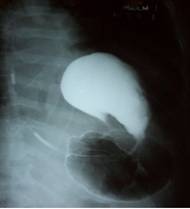

Se le realiza ultrasonido abdominal encontrándose gran dilatación gástrica con abundante contenido líquido en su interior. En la radiografía de tórax posteroanterior (figura 1) y en la simple de abdomen se observaba una gran distensión gástrica con un nivel hidroaéreo amplio que ocupaba todo hipocondrio izquierdo elevando significativamente el hemidiafragma.

Fig. 1: Rayos X de tórax y abdomen superior PA, marcador a la izquierda, muestra elevación del hemidiafragma izquierdo con gran dilatación gástrica y nivel hidroaéreo amplio.